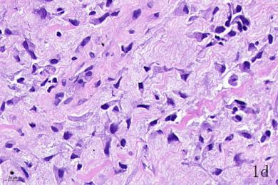

NDN(Necdin)属于黑色素瘤抗原(MAGE)家族,由60多个基因构成共享高度保守的MAGE同源结构域(MHD)[6,7]。最近几年的研究提出NDN是一种新的抑癌基因,其在卵巢癌[8]、乳腺癌[9]和黑色素瘤[10]等的组织和细胞系中低表达,过表达NDN可以抑制其生长,但NDN在骨肉瘤中的作用及机制尚不清楚。为探讨NDN在骨肉瘤中的作用及途径,我们收集了骨肉瘤患者的石蜡标本以及临床信息,对其进行了免疫组化检测及生存分析通过对骨组织和骨肉瘤HE染色发现,骨组织组,骨密质呈板层状,陷窝中可见骨细胞呈梭形排列( 图1 a 1b) ;骨肉瘤组,瘤细胞呈多角形,核大深染,核分裂多见,瘤细胞呈车辐状排列,瘤细胞间可见少量肿瘤性骨质形成(图1c1d)。同时通过免疫组化发现,NDN表达主要位于细胞的胞核中。NDN在骨肉瘤组织中的表达率为29.4%(15/51)(图1c1d),明显低于瘤旁骨组织阳性表达率80%(8/10)(图1a1b)。